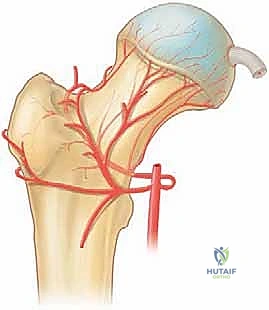

لفهم أهمية جراحة منظار الورك، يجب أولاً أن نفهم التكوين التشريحي المعقد لهذا المفصل الحيوي. مفصل الورك هو مفصل من نوع "الكرة والتجويف" (Ball and Socket Joint).

* الكرة: هي رأس عظمة الفخذ (Femoral Head).

* التجويف: هو جزء من عظمة الحوض يُعرف باسم الحُق (Acetabulum).

يُغطى كل من الكرة والتجويف بطبقة ناعمة من الغضروف المفصلي الذي يسمح للعظام بالانزلاق بسلاسة فوق بعضها البعض. كما يحيط بحافة التجويف حلقة من الغضروف الليفي القوي تُسمى الشفا الغضروفي (Labrum). يعمل الشفا كختم مطاطي يحافظ على السائل الزلالي داخل المفصل ويزيد من استقراره.

منظار الورك هو إجراء جراحي طفيف التوغل (Minimally Invasive) يتيح للجراح رؤية داخل مفصل الورك دون الحاجة إلى عمل شق جراحي كبير. يتم ذلك من خلال إدخال كاميرا دقيقة جداً (Arthroscope) متصلة بشاشة عرض عالية الدقة (4K) عبر شقوق صغيرة لا تتجاوز نصف سنتيمتر في الجلد.

من خلال هذه الرؤية المكبرة والواضحة، يستطيع الأستاذ الدكتور محمد هطيف فحص وتشخيص الأضرار بدقة متناهية، ثم إدخال أدوات جراحية دقيقة عبر شقوق أخرى صغيرة لإصلاح التمزقات، أو إزالة الشظايا العظمية، أو تقليم الغضاريف التالفة.